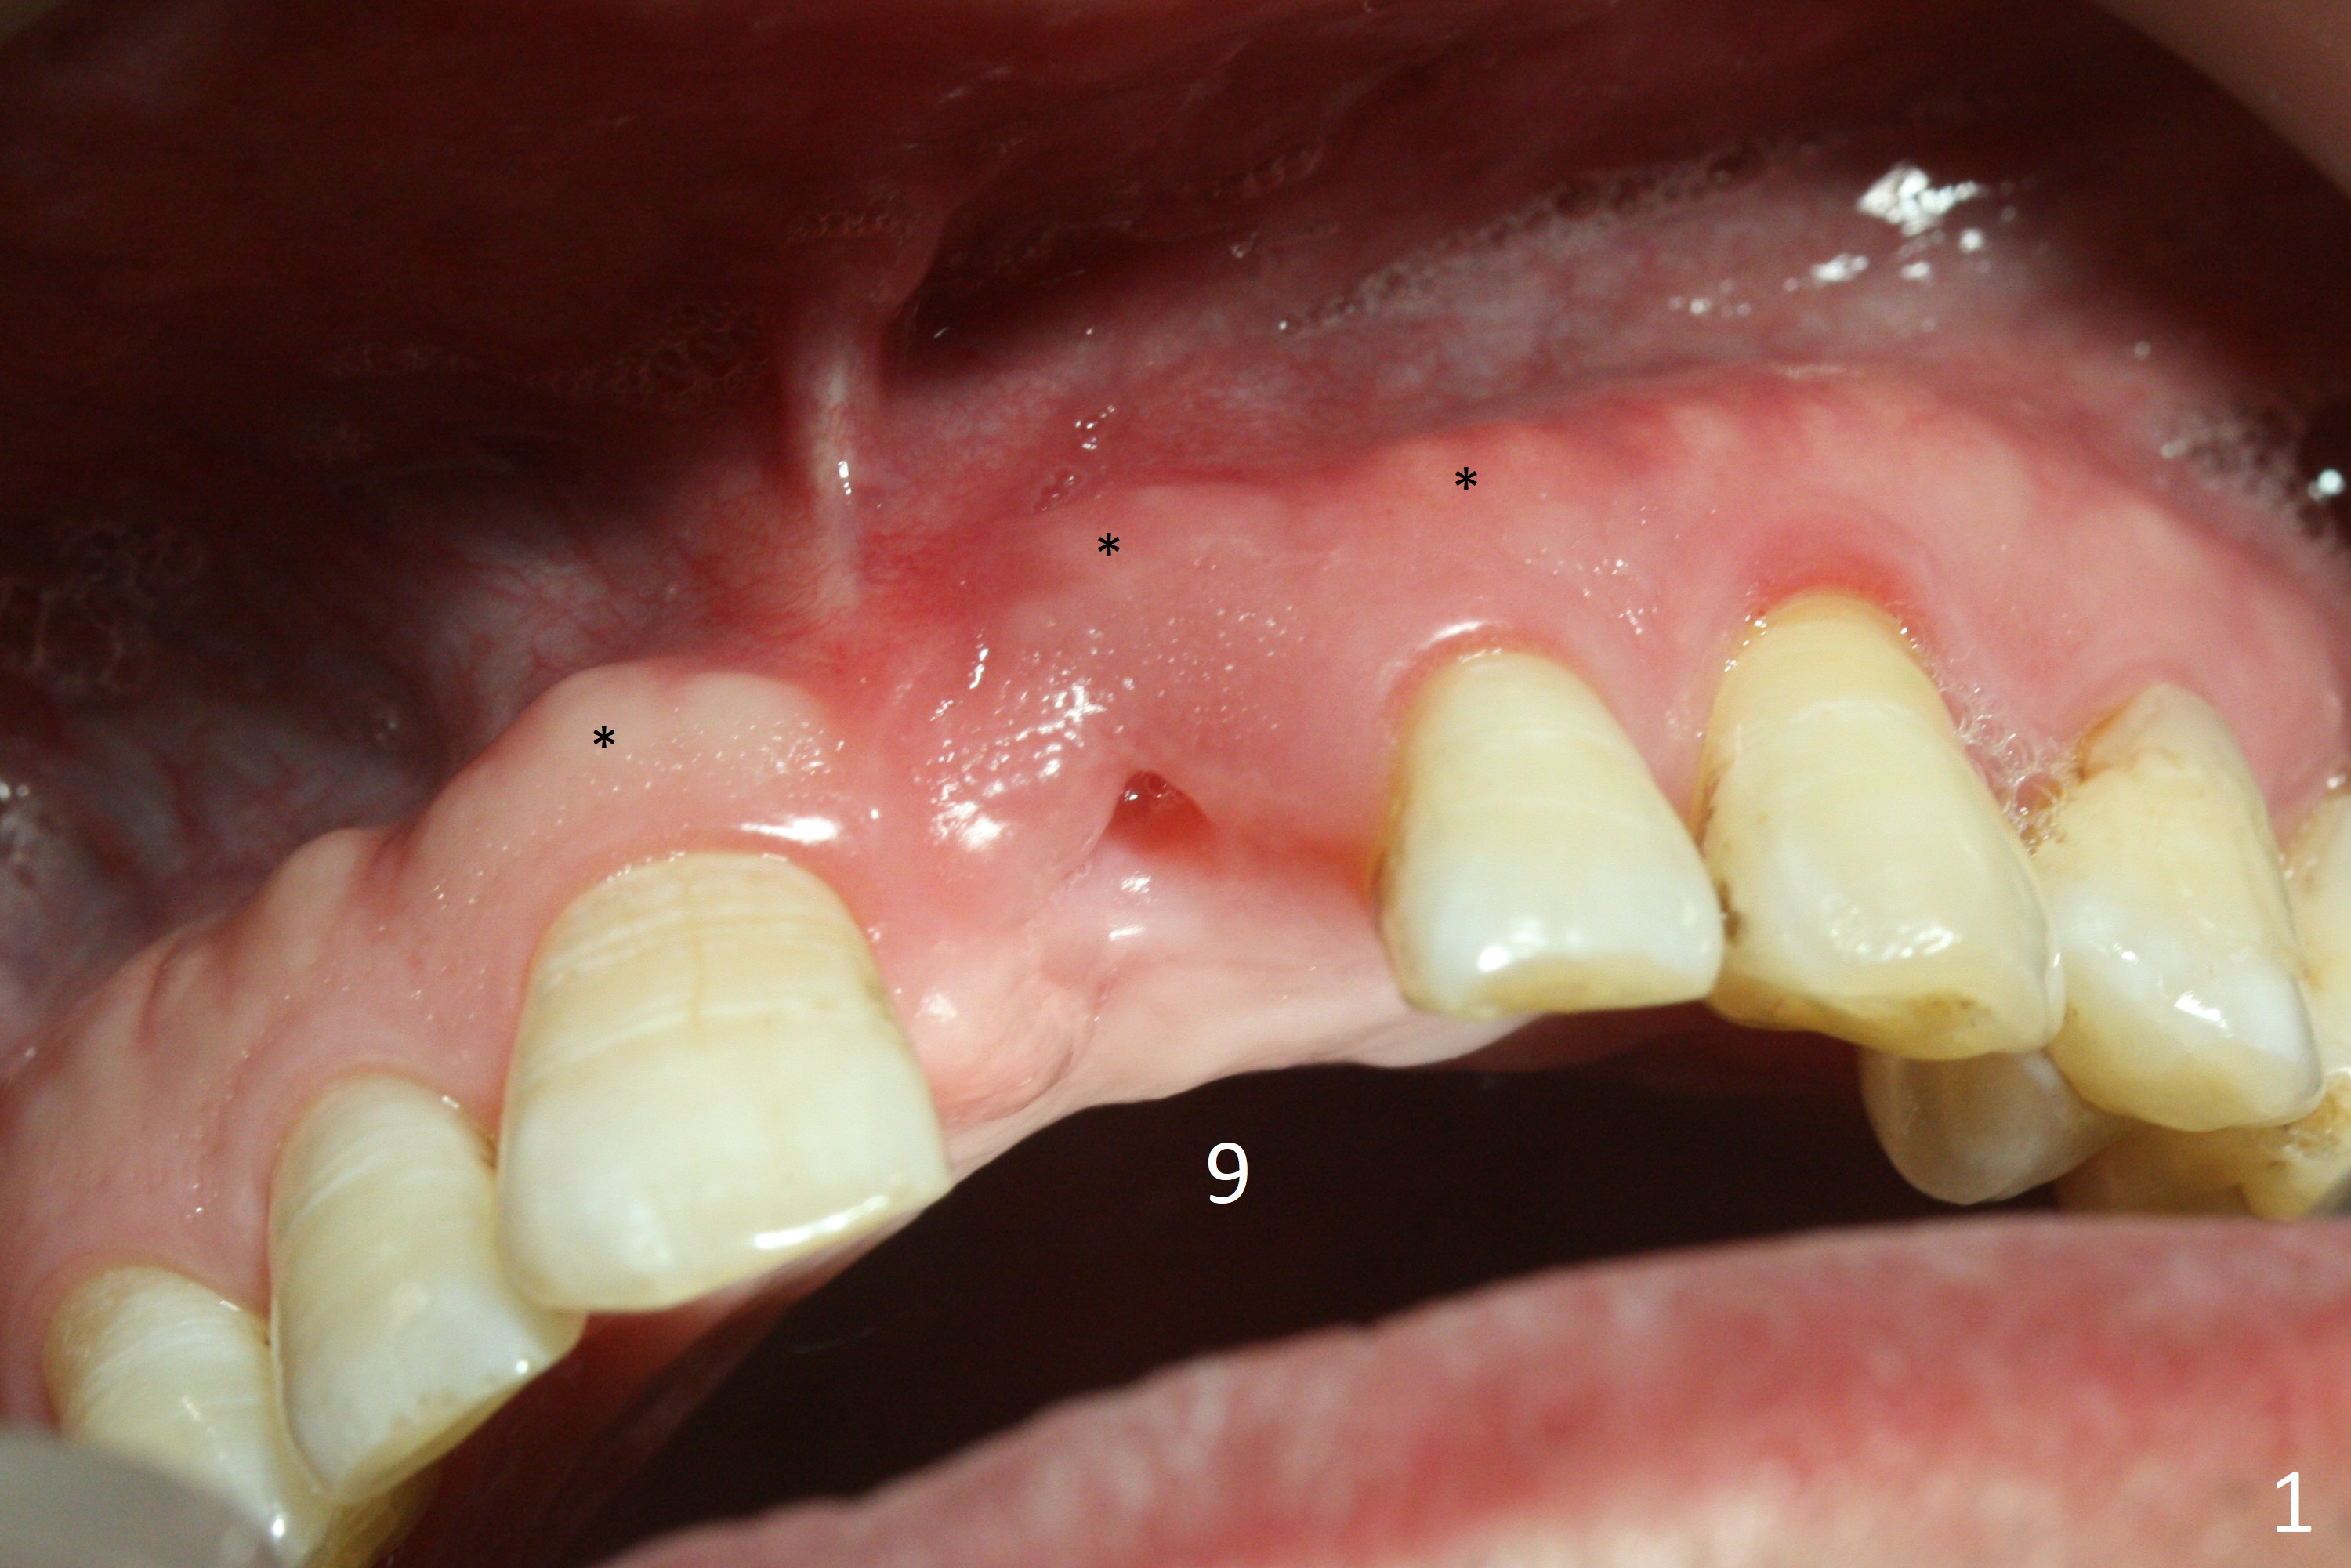

A 57-year-old man has lost the tooth #9 for 1-2 weeks (Fig.1,2). Although the buccal gingiva is recessive (cosmetically compromised), the middle and apical one thirds of the buccal plate appear to be minimally atrophic because of exostosis (Fig.1 *). An implant will be placed as palatal as possible (Fig.3). Use bone gauge to measure bone width. If the alveolus is atrophic, either use 3.5x13 mm implant or 1-piece (DIO or Tatum if there is a angulation problem). Prepare Planning Kit if IS implant is used. Adjust the opposing implant FPD, if needed.